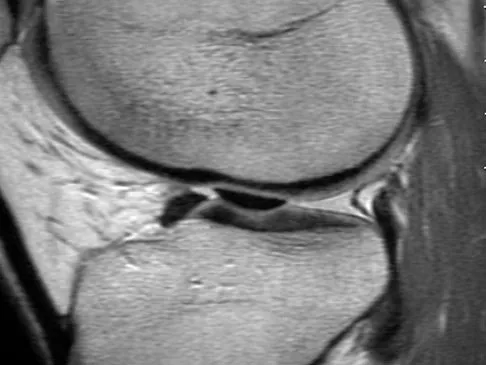

A 15-year-old girl reports a 6-month history of activity-related knee pain and swelling. A radiograph, MRI scan, and biopsy specimen are shown in Figures 21a through 21c. What is the most likely diagnosis?

Explanation

The epiphyseal location on the radiograph and MRI scan and the histologic findings of polyhedral cells separated by a chondroid matrix with pericellular, lattice-like "chicken wire" calcification all suggest chondroblastoma. Although giant cell tumors of bone typically occupy an epiphyseal location, they are rare in children and when present are often metaphyseal in skeletally immature patients. Enchondromas and osteoblastomas are generally metaphyseal and, along with giant cell tumors, have very different histology than seen here. Chondromyxoid fibromas are typically metaphyseal in location. Huvos AG: Bone Tumors: Diagnosis, Treatment, and Prognosis. Philadelphia, PA, WB Saunders, 1991, pp 295-313.